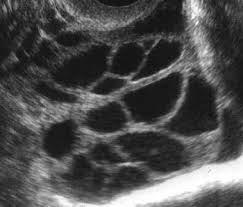

met zo'n echo's weet je dan exact waar je mee bezig bent en vooral wanneer je moet bezig zijn hahahhahaa